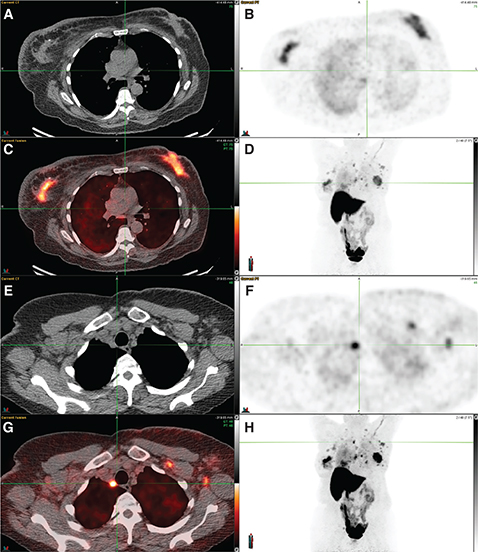

Fig 1

Figure 1. 18F-FDG PET/CT in carcinoma breast. A female with lump in the left breast, which was proven to be infiltrating ductal carcinoma on histopathology. Clinical stage was T2N1Mx with palpable axillary lymph nodes. 18F-FDG PET/CT was performed for staging the disease as part of pre-operative workup, which showed multiple foci of increased FDG uptake in the chest and upper abdominal region on the MIP image (A). The trans-axial CECT and fused PET/CT images showed a FDG avid heterogeneously enhancing lesion in the upper outer quadrant of left breast with multiple satellite nodules (B, C), FDG avid enlarged left level I axillary lymph nodes (D, E), a FDG avid sub centimeter right internal mammary lymph node (F, G), lung nodules (H, I) and a FDG avid hypodense lesion in the liver (J, K). The final stage post PET/CT was T3N1M1, which led to a change in management from surgery to systemic chemotherapy as patient’s classification was changed from having an operable breast cancer to an inoperable breast cancer with metastatic disease.